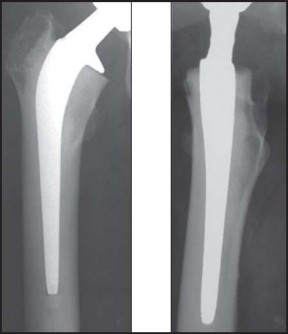

استبدال مفصل الورك الكلي بالإسمنت هو إجراء جراحي ناجح للغاية يعالج آلام الورك الشديدة ويستعيد وظيفة المفصل. يتضمن تثبيت غرسة الفخذ باستخدام إسمنت عظمي خاص، وتعتمد نتائجه الممتازة على دقة الخطوات الجراحية لضمان تثبيت قوي ومستقر يدوم طويلاً.

تقنية الإسمنت للفخذ، التي تُعد محور حديثنا، هي طريقة راسخة لتثبيت المكون الفخذي (الجزء الذي يتم إدخاله في عظم الفخذ) من المفصل الصناعي باستخدام إسمنت عظمي خاص. يضمن هذا الإسمنت استقرارًا فوريًا وقوة تحمل عالية، مما يجعله خيارًا ممتازًا للعديد من المرضى، وخاصة كبار السن وذوي العظام الضعيفة. ستكتشف في هذا الدليل لماذا تُعد هذه التقنية خيارًا موثوقًا به، وكيف يمكن أن تُحدث فرقًا حقيقيًا في حياتك.

- الدليل الشعاعي على التآكل الشديد: تُظهر الأشعة السينية تآكلًا كبيرًا في الغضروف، وتضيق